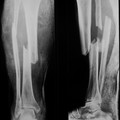

В подтверждение привожу снимки пациента И., 66 лет, поступившего с тяжелой сочетанной травмой через 3 суток после получения травмы. Объективно при поступлении - огромный, болезненный, напряженный отек голени, парестезии и ослабление пульсации на стопе. Прооперирован в день поступления. Все сделано так, как было описано выше. В послеоперационном периоде все признаки синдрома быстро пошли на спад. Начал приступать на конечность через 3 суток после операции, через две недели давал умеренную нагрузку, а через месяц мог ходить без дополнительных средств опоры.